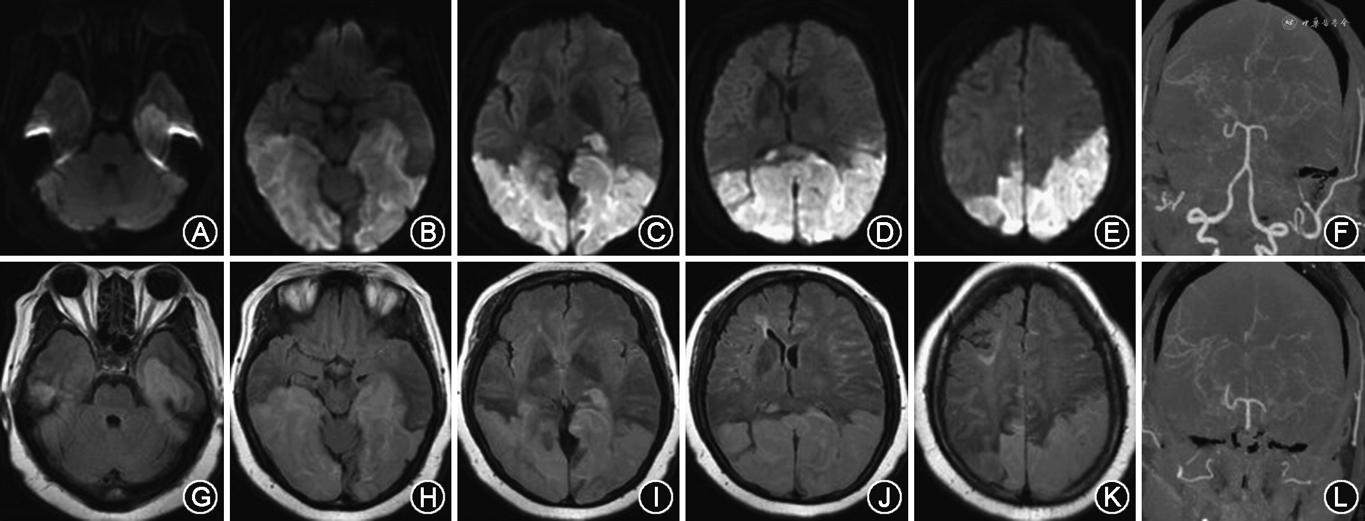

临床资料 患者女性,49岁,农民,初中文化,因“突发双眼失明4 d,加重伴右侧肢体无力6 h”为代主诉于2019年3月21日入院。4 d前(2019年3月17日)患者活动后突然出现双眼失明,视力丧失,伴有恶心、呕吐,呕吐3次,均为胃内容物,无头晕、头痛,无饮水呛咳,遂至当地县医院住院治疗(具体治疗方案不详)。3月21日上午6时前患者出现右侧肢体无力,右上肢持物不稳,右下肢不能抬起,伴左侧颞部疼痛,烦躁不安,在当地医院治疗效果欠佳,为求进一步治疗,遂至我院,以“脑梗死”收入我科。自发病以来,患者间断烦躁不安,精神差,饮食、睡眠差,大小便正常,体力差,体重无特殊变化。既往史:患“高脂血症”10年、“心房颤动”5年、“高血压病、2型糖尿病”1年,均未服用药物。入院体格检查:体重80 kg,血压176/102 mmHg(1 mmHg=0.133 kPa)。意识清楚,轻度烦躁不安。言语流利,近期记忆力减退,远期记忆力正常,计算力稍减退,理解判断力正常。双侧额纹对称,双侧瞳孔等大等圆,直径约2.5 mm,光反射灵敏。双眼全盲,双侧鼻唇沟对称,口角无歪斜,伸舌居中。右上肢肌力Ⅲ+级,右下肢肌力Ⅱ级,左侧肢体肌力Ⅴ-级,右侧肢体肌张力降低,左侧肢体肌张力正常。四肢腱反射(++),双侧肢体深、浅感觉正常。右侧肢体指鼻试验、跟膝胫试验欠配合,左侧肢体指鼻试验、跟膝胫试验正常。双侧巴宾斯基征阳性。颈软,克尼格征、布鲁金斯征均阴性。NIHSS评分:9分。精神神经问卷(NPI)评分:4分。辅助检查:葡萄糖 14.1 mmol/L,糖化血红蛋白9.04%,低密度脂蛋白4.17 mmol/L。余血生化、风湿免疫、肿瘤标志物均正常。头颅MRI示:DWI、FLAIR双侧颞顶枕叶高信号,双侧颞顶枕叶急性脑梗死(图1)。头颈联合CTA示:双侧颈内动脉、大脑前、中动脉闭塞,走行区见多发侧支循环形成;双侧大脑后动脉P2段闭塞伴走行区多发侧支循环形成(图1F、L)。

患者中年女性,急性动态起病,烦躁不安,近期记忆力减退、计算力减退,定位于边缘系统或双侧大脑皮质传导纤维受累;双眼全盲,定位于双侧枕叶视皮质中枢受累;双侧肢体中枢性瘫痪,定位于双侧皮质脊髓束受累,故综合定位于椎基底动脉系统。患者既往有心房颤动、高血压病、2型糖尿病、高脂血症等高危因素,头颅MRI示双侧颞顶枕叶急性脑梗死,故定性脑梗死明确。其病因及发病机制考虑可能有以下几点:(1)低灌注/栓子清除障碍:该患者中年女性,既往有动脉粥样硬化等高危因素,MRI示双侧后循环急性梗死,CTA示双侧颈内动脉和大脑前、中动脉闭塞,走行区多发细小侧支循环形成,双侧PCA P2~P4段闭塞伴走行区多发细小侧支循环形成;可见前循环血供主要是由后循环及颅底异常血管网代偿,当患者出现恶心、呕吐等诱发因素容易导致循环血量减少,后循环代偿不足导致低灌注/栓子清除障碍,加重后循环缺血导致急性脑梗死发生。(2)栓塞机制:该患者既往有心房颤动病史,此次急性动态起病,症状迅速达高峰,影像学示双侧后枕叶大面积梗死,故心源性栓塞不能排除;但不支持点是患者心脏超声未见显著附壁血栓,仍需进一步完善经食道超声心动图检查。(3)其他原因导致后循环血管病变:目前烟雾病或烟雾综合征的病因不明,烟雾病导致双侧前循环逐渐狭窄闭塞,是否也会累及后循环导致双侧PCA逐渐狭窄闭塞出现梗死。本例患者双侧PCA P2~P4段闭塞伴侧支循环,有动脉粥样硬化高危因素,因此后循环血管病变不能排除,患者因经济原因拒绝做DSA。综上所述,该患者病因可能存在大动脉粥样硬化性低灌注/栓子清除障碍、心源性栓塞、烟雾综合征等多种病因,故综合考虑不明原因型栓塞可能性较大。

双侧PCA闭塞具体的病因及发病机制目前尚未明确。据文献报道,双侧PCA梗死的病因包括心源性栓塞、大动脉粥样硬化性/隐源性栓塞、椎动脉或基底动脉夹层、血管收缩、凝血功能障碍和烟雾综合征等。其中,心源性栓塞是PCA皮质梗死最常见的病因[7]。然而,仍有25%的患者出现双侧PCA梗死的病因不明[8]。解剖学研究发现,大脑后动脉分为4段:P1交通前段、P2环池段(P2A前段、P2P后段)、P3四叠体段、P4距裂段。结合本例患者CTA可见双侧PCA-P2P后段出现闭塞,导致脉络膜后外动脉、颞后动脉、颞下动脉、顶枕动脉、距裂动脉闭塞,出现双侧枕叶、颞叶底部、海马回向后外方、膝状体等部位梗死。